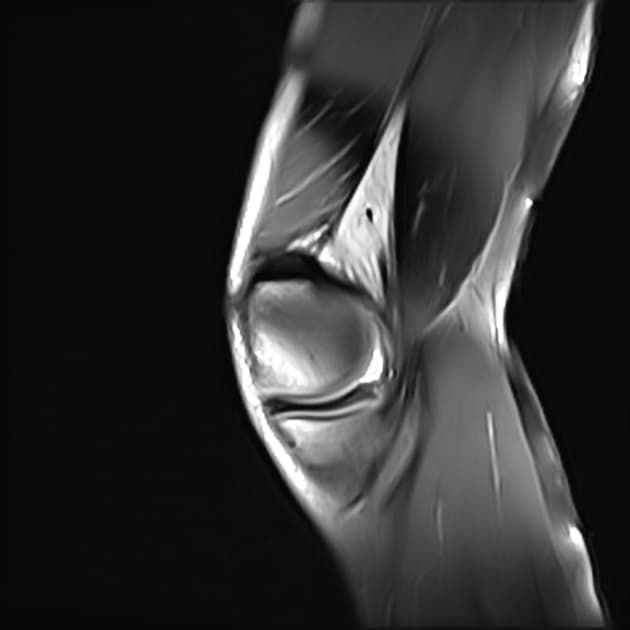

- Đứt thân và sừng sau của sụn chêm bên, gây ra hiện tượng một phần đáng kể của sụn chêm bị lật về phía trước và vào trong, nằm trong khe gian lồi cầu.

- Trên các hình ảnh cắt dọc, thấy dấu hiệu "sụn chêm ảo" (ghost meniscus sign) ở phía sau.

- Ngoài ra, thấy dấu hiệu "tam giác kép" (double delta sign) ở phía trước.

- "Dấu hiệu 'sụn chêm ảo' trên hình cộng hưởng từ cắt dọc cho thấy sự vắng mặt của tổ chức sụn chêm bình thường tại vị trí dự kiến, gợi ý rách di lệch."

- "Dấu hiệu 'tam giác kép' là phát hiện cộng hưởng từ quan trọng trong tháp mạc gối lật ngược, biểu hiện mảnh sụn di lệch nằm kề sừng trước, tạo thành hai cấu trúc hình tam giác."

Tháp mạc gối lật ngược là một dạng đặc biệt của rách dạng xô, thường gặp ở sụn chêm bên. Tình trạng này xảy ra khi một vết rách dọc dọc cho phép một mảnh lớn của sụn chêm—thường là thân và sừng sau—di lệch về phía trước và vào trong vào khe gian lồi cầu. Sự di lệch này dẫn đến 'dấu hiệu sụn chêm ảo', khi giường sụn chêm nguyên bản trông trống rỗng trên hình ảnh cắt dọc. Mảnh sụn di lệch nằm kề sừng trước, tạo thành 'dấu hiệu tam giác kép'—hai cấu trúc hình tam giác riêng biệt có cường độ tín hiệu thấp, đại diện cho sừng trước bình thường và mảnh sụn bị lật. Các phát hiện đi kèm như tổn thương dập xương, dịch khớp và căng giãn dây chằng thường gặp do cơ chế chấn thương. Việc nhận diện sớm trên cộng hưởng từ rất quan trọng để lên kế hoạch phẫu thuật, vì tổn thương này thường cần được giảm chỉnh và sửa chữa nội soi.